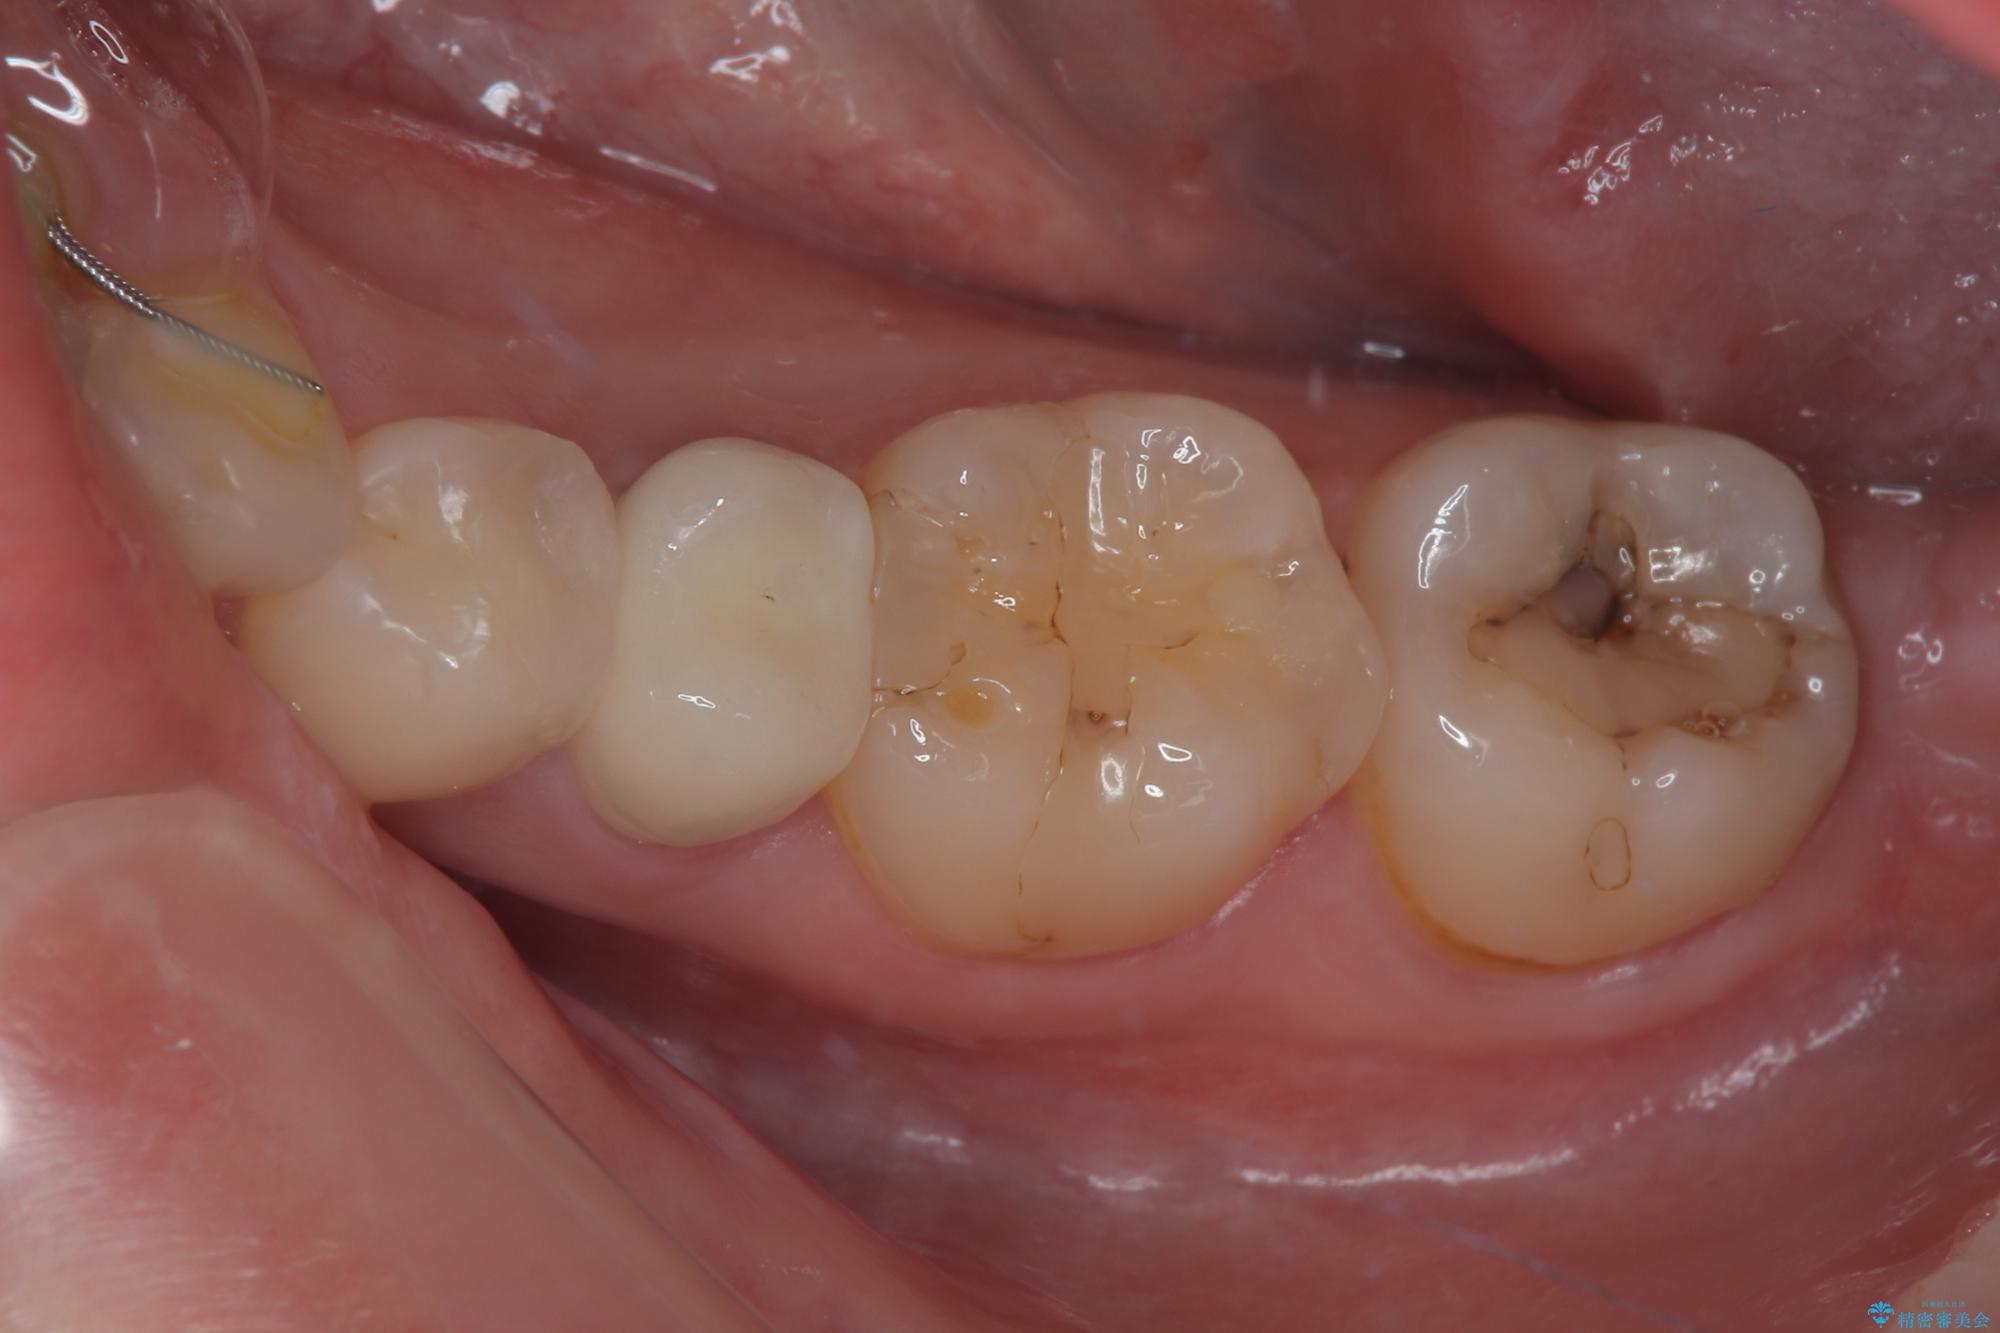

- 左下の被せものが割れたとのことで来院された患者様です。検査の結果、左下の前から4番目の歯はセラミックインレー修復、左下の5番目のところはオールセラミッククラウンによる補綴治療を行っていくことにしました。

拡大鏡視野下で被せもの、虫歯の除去を行い、オールセラミッククラウン、セラミックインレーに適した形に整えました。

適合の良い被せものが入り、審美面も気に入っていただけました。被せものが割れていたという経緯もあったため少しだけ被せものの厚みを多めに確保してあります。